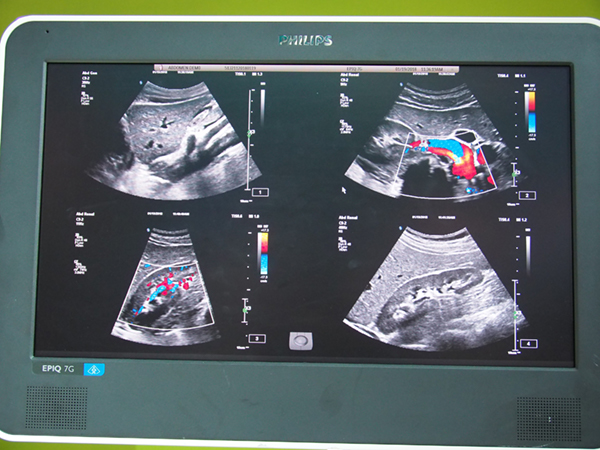

このほか会場では,腹部系アプリケーションが搭載された「EPIQ 7G」など,超音波診断装置のラインアップを展示。EPIQ 7Gは,高精密ビームフォーマーと超並列処理を組み合わせた独自のビームフォーミングテクノロジー“nSIGHT”により,空間分解能,時間分解能,組織均一性がトレードオフとならずに,診断価値の高い画像を提供することができる。

腹部領域向けのプレミアム装置「EPIQ 7G」

“nSIGHT”により診断価値の高い画像を提供